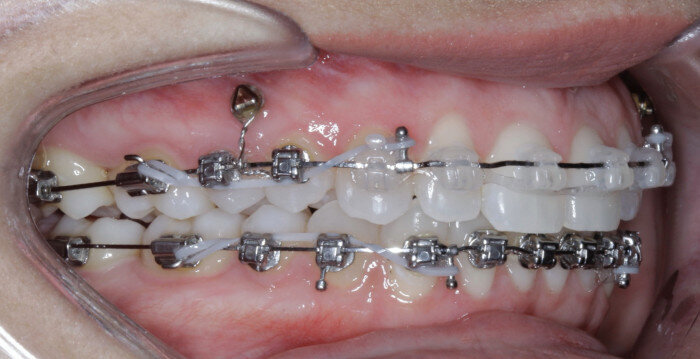

The same protocol is used, in which TADs are placed at the second visit with the 14 × 25 mm Cu–NiTi wire and tied to the archwire using elastic thread. Once in larger Cu–NiTi and stainless-steel wires, the TADs are tied to the wire using a power chain or NiTi closing springs (Figs. 17 & 18).